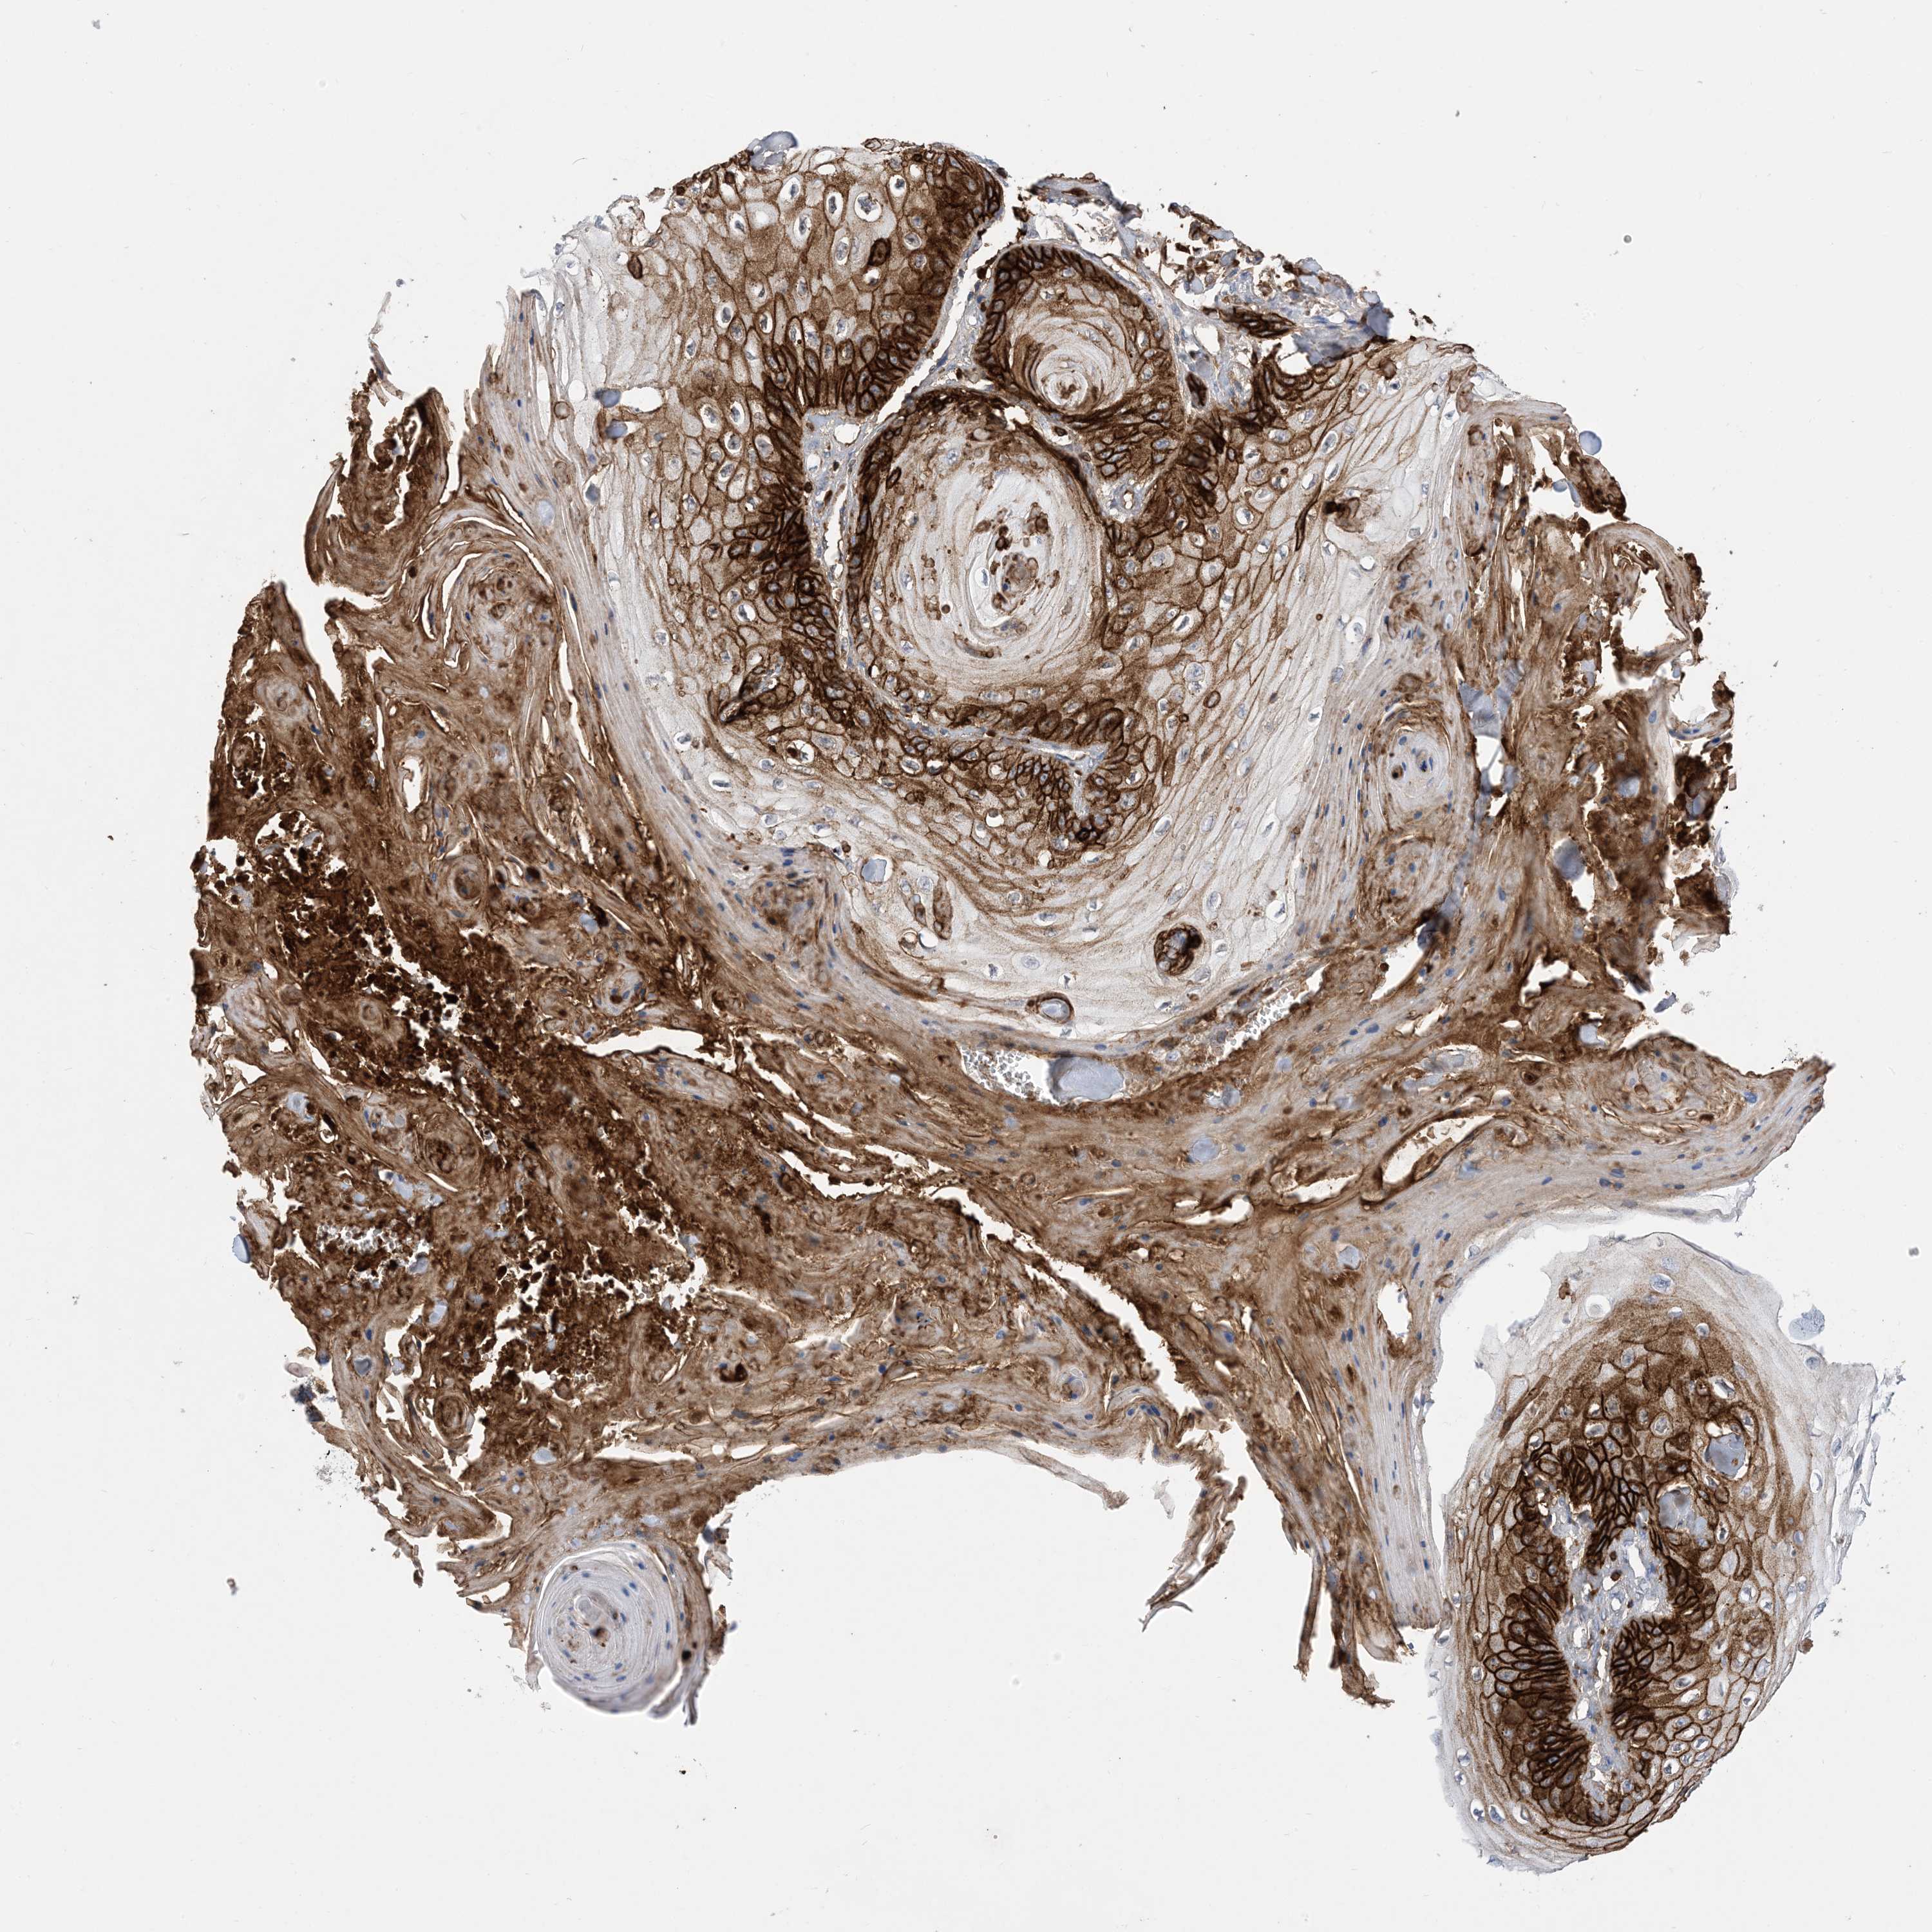

Basal cell and squamous cell cancer

SKIN CANCER - Protein expressioni

A mouse-over function shows sample information and annotation data. Click on an image to view it in a full screen mode. Samples can be filtered based on level of antibody staining by selecting one or several of the following categories: high, medium, low and not detected. The assay and annotation is described here.

Each image is clickable and will lead to virtual microscopy that enables deeper exploration of all samples and also displays staining intensity scores, fraction scores and subcellular localization as well as patient and tissue information for each sample.

Antibody HPA049265

Basal cell carcinoma